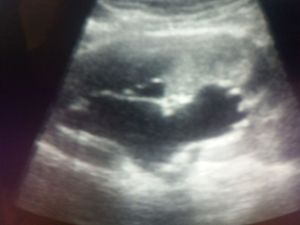

What are you see?????

Kidney

Ultrasound

Hydronephrosis